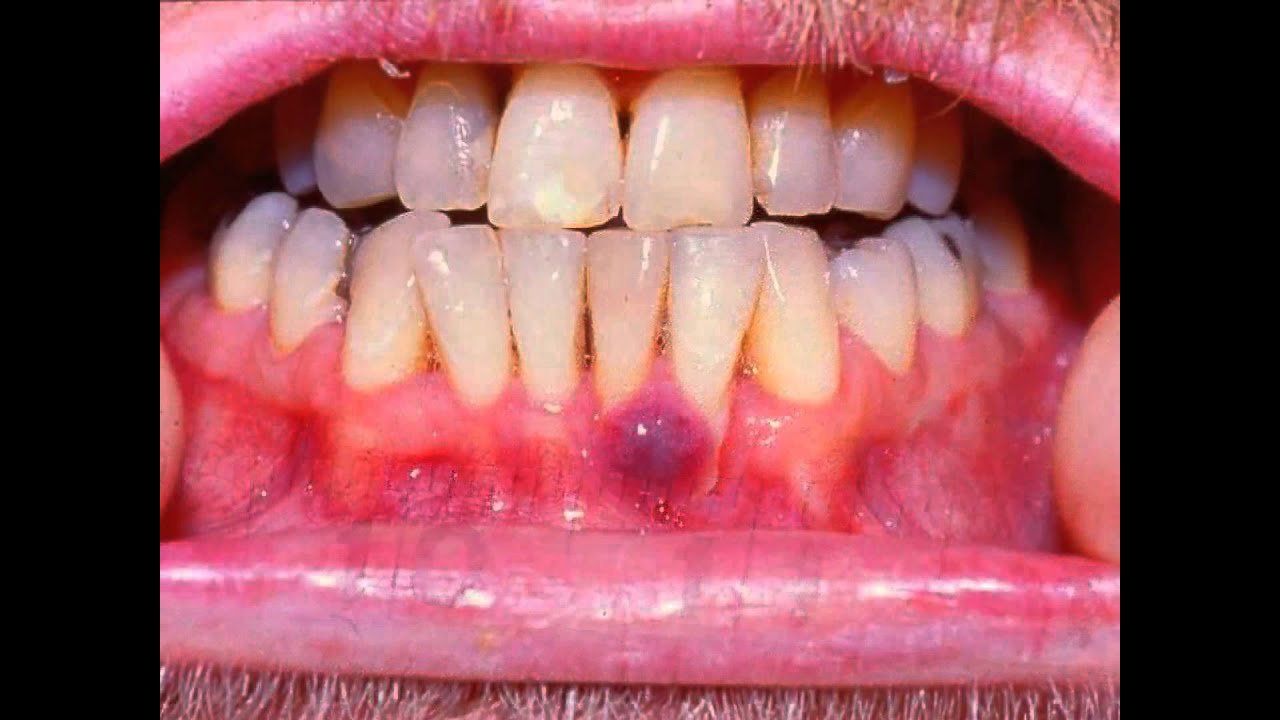

Ung thư Kaposi (tên tiếng anh là Sacorma Kaposi) là bệnh lý ác tính toàn thân liên quan đến tổn thương tại biểu mô mạch máu có tiến triển chậm. Đây là bệnh lý đặc trưng với tình trạng phát triển bất thường của các khối u ác tính xuất hiện dưới da và trong lớp niêm mạc các vùng mũi, họng, miệng hoặc niêm mạc những vùng khác trên cơ thể. Bệnh biểu hiện chủ yếu ở da và niêm mạc với những khối u ác tính màu đỏ hoặc tím và đau, xuất hiện trong khoảng 30% các trường hợp. Trong những trường hợp di căn đến những cơ quan khác, bệnh ung thư Kaposi có thể gây ra nhiều biến chứng khác như khó thở, suy hô hấp cấp nếu di căn đến phổi hoặc chảy máu nếu cơ quan ảnh hưởng là dạ dày.

4. Triệu chứng ung thư Kaposi

Bệnh ung thư Kaposi là bệnh lý ác tính có biểu hiện chính ở da và niêm mạc dưới dạng những thương tổn tăng sinh dạng u đơn độc có cuống hoặc tập trung thành từng đám. Chúng thường có kích thước nhỏ, màu tím hoặc đỏ, thường xuất hiện trên da vùng cẳng chân. Một số vị trí khác trên cơ thể có thể bắt gặp những tổn thương tương tự là da vùng mặt, niêm mạc mũi, họng, miệng. Bệnh ung thư Kaposi có quá trình diễn tiến chậm nhưng vẫn có thể có di căn đến các cơ quan khác trong cơ thể, thường thấy nhất là hạch bạch huyết, hệ tiêu hóa, phổi. Khi ung thư Kaposi di căn đến đường tiêu hóa kéo dài từ hầu đến hậu môn, bệnh nhân có thể gặp phải các biểu hiện khác trên lâm sàng như đau bụng, nôn ra máu hoặc đi cầu phân đen do xuất huyết niêm mạc dạ dày. Khi bệnh ung thư Kaposi lan đến hai phổi, bệnh nhân có thể gặp phải tình trạng khó thở, suy hô hấp cấp tính.

Thiết lập chẩn đoán bệnh ung thư Kaposi cần dựa trên các biểu hiện lâm sàng và các phương tiện cận lâm sàng khác. Bệnh có biểu hiện đặc trưng trên lâm sàng, nhất là ở những bệnh nhân có hệ miễn dịch suy giảm, bao gồm:

- Các u nhỏ đơn độc hoặc các mảng thay đổi sắc tố màu đỏ, tím

- Vị trí xuất hiện các tổn thương thường ở các nếp căng da

- Có sự thay đổi màu sắc từ đỏ hoặc tím sang xanh, vàng xung quanh các khối u, phù hợp với tổn thương dạng xuất huyết.

- Tổn thương ở da lan rộng, có thể vào đến các vùng niêm mạc mũi, hầu họng, có thể có tình trạng phù bao quanh.